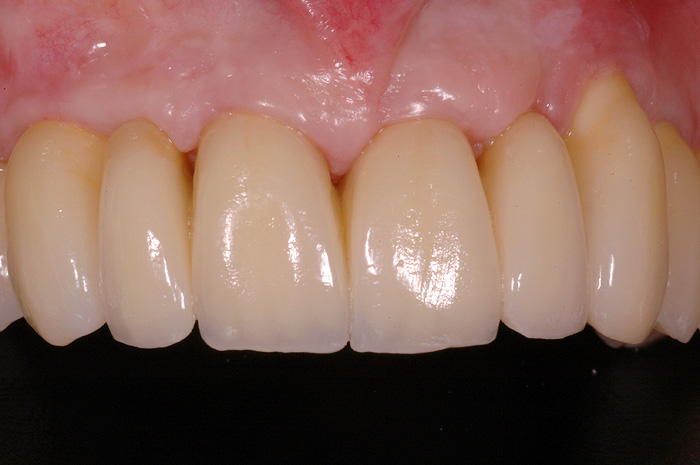

Fallbeispiel

Zum Vergrössern klicken